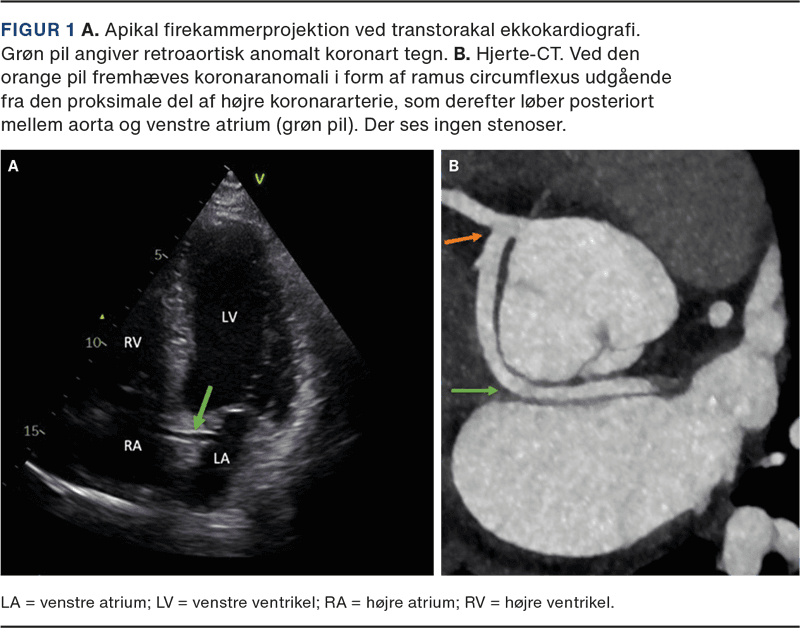

Ved indlæggelsen fandt man normale vitalværdier fraset et forhøjet blodtryk på 161/101 mmHg. Biokemien, inklusive troponinniveau, var upåfaldende. Røntgen af thorax var normalt. Et 12-aflednings-ekg viste sinusrytme med en frekvens på 84 bpm, normal overledning og ingen tegn på belastning eller iskæmi. En transtorakal ekkokardiografi var overvejende upåfaldende med normal biventrikulær systolisk funktion og uden valvulopati, pulmonal hypertension, aortopati eller perikardieekssudat. Fra flere projektioner bemærkedes et karspor foreneligt med retroaortisk anomalt koronart (RAC) tegn, hvilket rejste mistanke om koronaranomali (Figur 1A).

Hjerte-CT’en viste koronaranomali i form af ramus circumflexus (Cx) udgående fra højre koronararterie uden interarterielt forløb (Figur 1B). Der blev ikke fundet nogen stenoser, og calciumscoren var 0. Patientens symptomer blev tilskrevet supraventrikulære ekstrasystoler samt stress, og han startede i et behandlingsforløb for stress via sin egen læge med symptomatisk bedring.